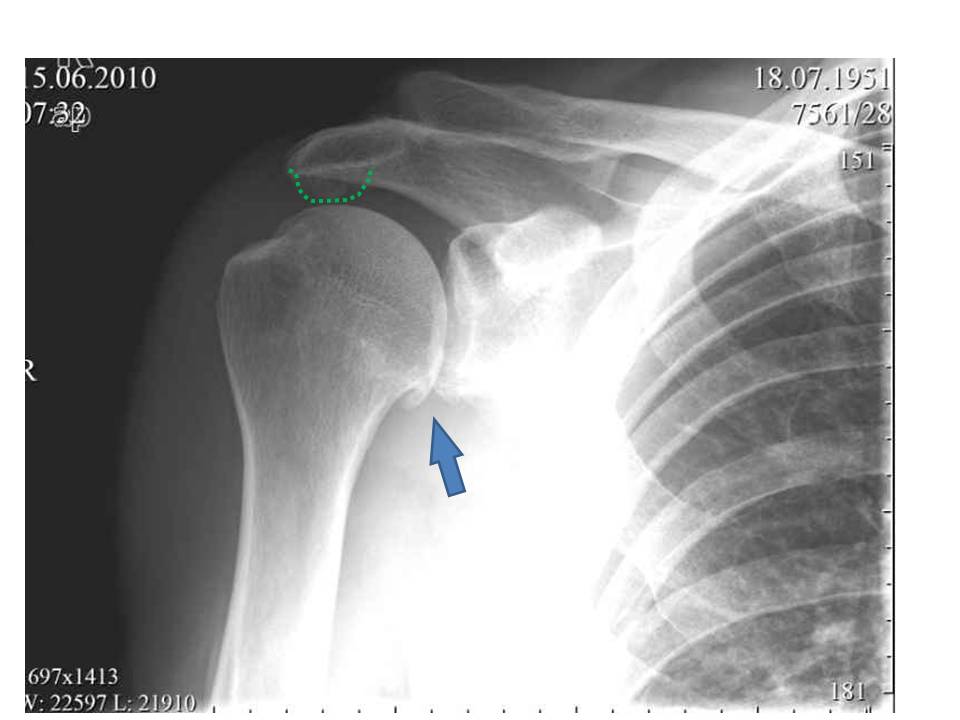

Рентгенография

Необходима для визуализации костных структур плечевого сустава. С помощью рентгенологического исследования врачи оценивают состояние клювовидно-акромиальной связки, акромиально-ключичного сустава и плечелопаточного соединения. При импиджменте специалисты выявляют децентрацию головки плечевой кости, патологические изменения большого бугорка, оссификацию связок и признаки артроза плечевого сустава.